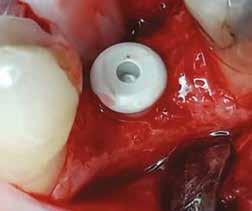

Egy 47 éves páciens jelentkezett nálunk egy alsó, hátsó foghiánnyal, ahol jelentős csontfelszívódást tapasztaltunk a moláris fogak korábbi eltávolítása miatt (1. ábra). Két implantátum körül is volt ínyrecesszió, illetve a keratinizált íny mennyisége minimális volt (kevesebb, mint 1 mm). 4 hónappal az implantációt követően ínykorrekciót végeztünk.

2–5. ábra: A metszések és a deepitelizáció. – 6–9. ábra: Félvastag lebeny. – 10. ábra: A nyelezett ínylebeny „bepróbálása”.

horizontális metszéssel kötöttük össze (2–5. ábra). A metszések hosszát és a köztük lévő távolságot minden esetben a lágyszövet augmentációhoz szükséges keratinizált szövet határozza meg. A lebeny deepitelizációját egy 15C-s szikepengével végeztük (6. ábra). Ezt követően félvastag lebenyt preparáltunk (7. ábra). A lebenyt apikálisan, az alapjáról belső, felületes metszéssel felszabadítottuk, hogy passzívan áthelyezhessük és rögzíthessük, feszülés nélkül. Meziális irányba 180 fokkal átforgattuk (8–9. ábra). A meziális papillát alagúttechnikával (tunnelling technique) készítettük elő a graft befogadására (10. ábra). Az így kialakított lebenyt a recipiens ágyban rögzítettük az újonnan kialakított vesztibulum alapjánál 5-0 nem felszívódó PTFE (Coreflon, IMPLACORE) varratokkal. A graftot behajtottuk az ínyszél alá és meziális oldalon rögzítettük PTFE varratokkal (11–14. ábra) A műtétet követően napi kétszeri, 0,12%-os klórhexidin tartalmú szájvízzel történő öblögetést javasoltunk a páciensnek, két héten keresztül. Gyulladáscsökkentésre 8 óránként 400 mg Ibuprofént javasoltunk, három napon keresztül. A páciens elmondása szerint sem fájdalmat, sem különösebb diszkomfortot nem tapasztalt. Ezt követően, további 4 héten keresztül, 0,2%-os klórhexidin tartalmú szájvízzel történő öblögetést javasoltunk a betegnek és instruáltuk, hogy lehetőleg ne mossa fogkefével az érintett területet. A varratokat egy héttel később távolítottuk el. A donor és a recipiens terület – 10 nappal a műtétet követően – kiválóan gyógyult (15–16. ábra). Az ezt követő kontrollokat a következő időpontokban ejtettük meg: kettő, illetve négy héttel a műtét után, majd három, hat és tizenkét hónappal később, ezt követően pedig félévente (17–20. ábra). Minden kontroll alkalmával professzionális fenntartó kezelést végeztünk a területen.